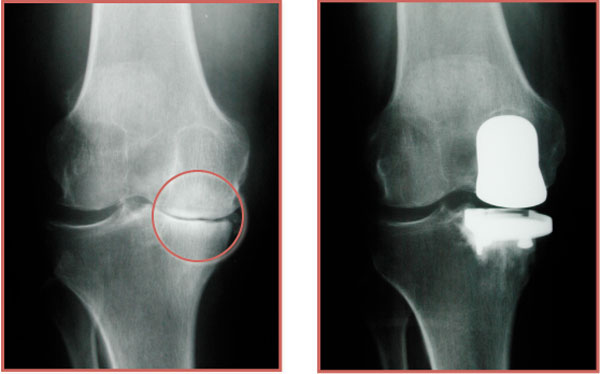

Partial knee replacement (PKR), also known as unicondylar or unicompartmental knee replacement, is a surgical procedure that replaces only the damaged portion of the knee joint, while preserving the healthy parts. Unlike total knee replacement, PKR focuses on restoring function by targeting one or two specific compartments of the knee.